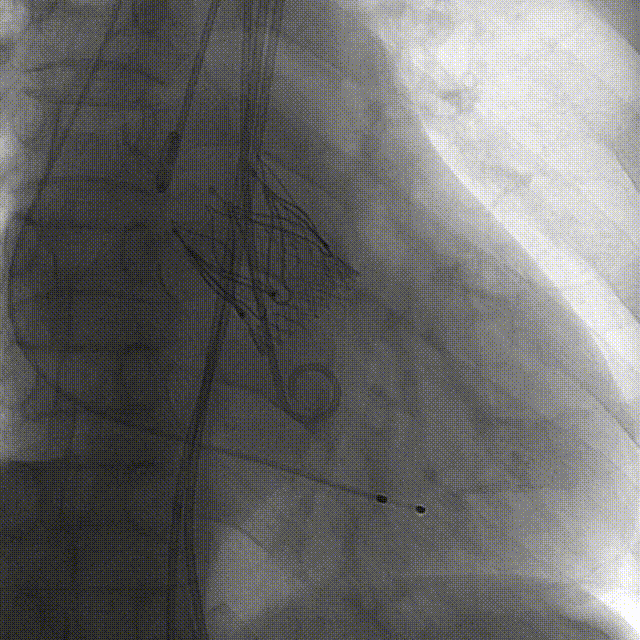

Case 4

重度反流心衰伴冠脉多支病变

(EF37%)

术前CT评估

根据瓣环与 LVOT-6 mm 平面,备后扩解决瓣上,避免瓣周漏,选择:M 号 TaurusTrio

手术过程:5A 标准化流程SOP

左冠造影

小右冠,弥漫性病变

LAD术后造影

根部造影

长鞘植入

输送器定位

右窦中心对齐

定位键窦对齐

无窦确认

右窦观察

左窦确认

深度确认

一键脱钩

术后造影